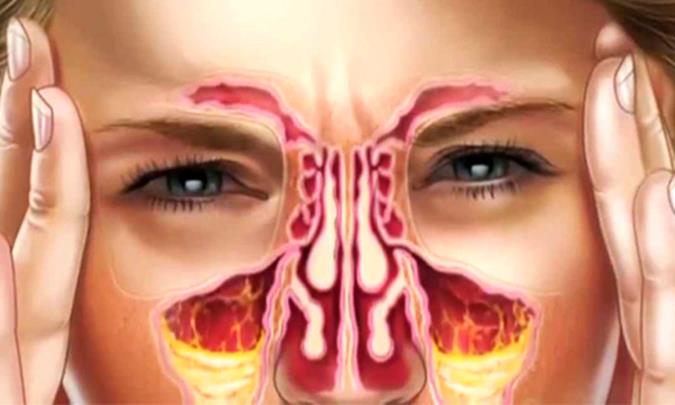

سینوزیت حاد باعث می شود تا فضاهای موجود در داخل بینی (سینوس ها) ملتهب و متورم شوند. این التهاب باعث می شود تا دیگر تخلیه این ناحیه به خوبی صورت نگرفته و در نتیجه مخاط در این قسمت تجمع پیدا کند. ابتلا به سینوزیت حاد ممکن است باعث شود تا نفس کشیدن از طریق بینی دشوار شده و ناحیه اطراف چشم و صورت فرد مبتلا متورم شود. علاوه بر این فرد مبتلا به سینوزیت حاد ممکن است دچار علائمی مثل درد شدید صورت یا سردرد شود.سینوزیت حاد بیشتر در اثر سرماخوردگی ایجاد می شود. اگر عفونت باکتریایی ایجاد نشود، بیشتر موارد در طی یک هفته تا 10 روز برطرف شده و درمان های خانگی ممکن است تمام موارد لازم برای درمان سینوزیت حاد باشد. سینوزیتی که با وجود درمان توسط پزشک بیش از 12 هفته به طول بیانجامد سینوزیت مزمن نامیده می شود.1

هنگامی که شما به سینوزیت مبتلا می شوید غشای مخاطی بینی شما، سینوس ها و گلو (بخش فوقانی دستگاه تنفس شما) ملتهب می شود. تورم مانع از باز شدن سینوس ها می شود و از تخلیه مخاط به صورت معمولی جلوگیری می کند که منجر به درد صورت و سایر علائم سینوزیت می شود.سینوس های بسته شده یک محیط مرطوبی را ایجاد می کنند که منجر به نگه داشته شدن آسان تر عفونت می گردند. سینوس هایی که عفونی می شوند نمی توانند ترشحات را تخلیه کنند و پر از چرک می گردند، که این امر منجر به علائم و نشانه هایی همچون ترشحات ضخیم، زرد و یا سبز رنگ و سایر علامت های عفونت می شود.

علائم حاد سینوزیت اغلب شامل موارد زیر می شود:ترشحات سبز، زرد غلیظی که از بینی یا پشت گلو خارج شود.

انسداد بینی یا گرفتگی بینی که باعث مشکل تنفس از بینی شود.

درد، حساسیت، تورم و فشار اطراف چشم، گونه، بینی یا پیشانی که هنگام خم شدن فرد شدت می گیرد.